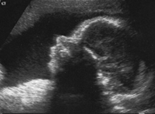

Prenatal Diagnostics / Ultrasound

- Malformation diagnostics

- Doppler sonography

- 3-D-Sonography